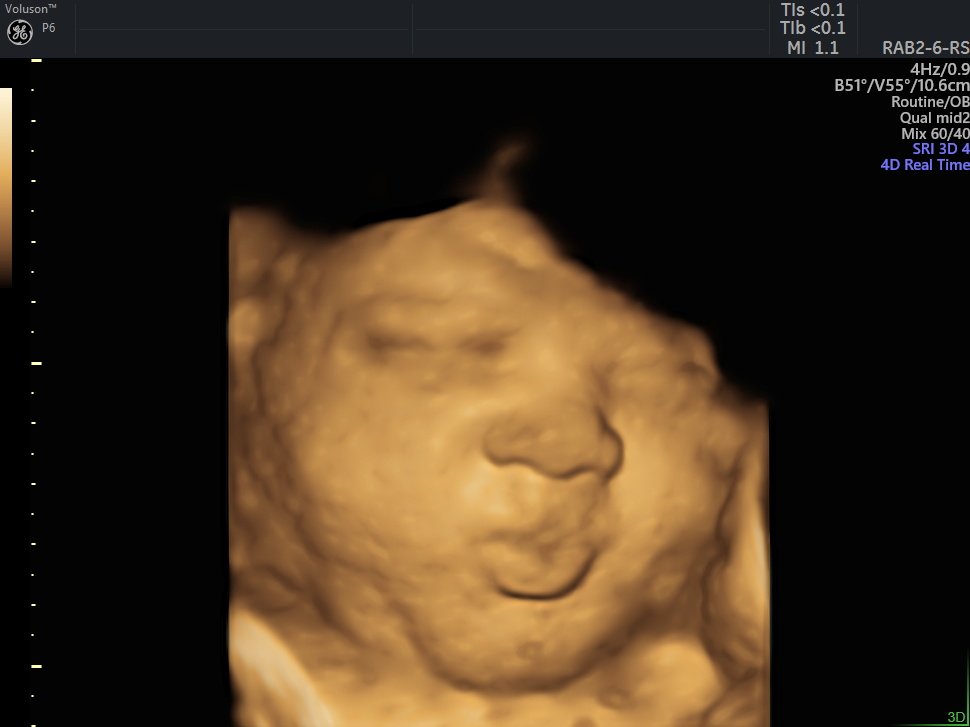

4 D Ultrasonografi

4 Boyutlu (Renkli) Ultrason ve Doppler Ultrasonografi